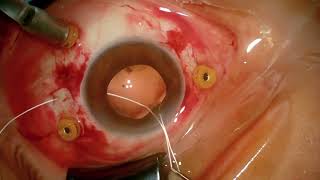

Intrascleral Gore-Tex for Dislocated Intraocular Lens Dropped nucleus and four-point scleral fixation (Akreos & Gore-Tex)

Dropped nucleus and four-point scleral fixation (Akreos & Gore-Tex) GORE-TEX SFIOL - Superior long term centration and stability of the IOL

Intrascleral Gore-Tex for Dislocated Intraocular Lens Dropped nucleus and four-point scleral fixation (Akreos & Gore-Tex)

Dropped nucleus and four-point scleral fixation (Akreos & Gore-Tex) GORE-TEX SFIOL - Superior long term centration and stability of the IOL